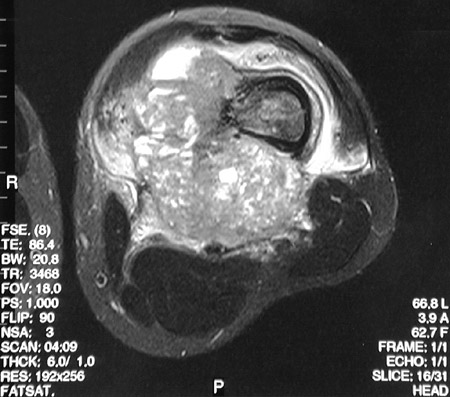

This T2 weighted axial FSE MRI scan with fat saturation reveals disruption of the bone cortex along with a mass extending into adjacent soft tissue in the distal femur.